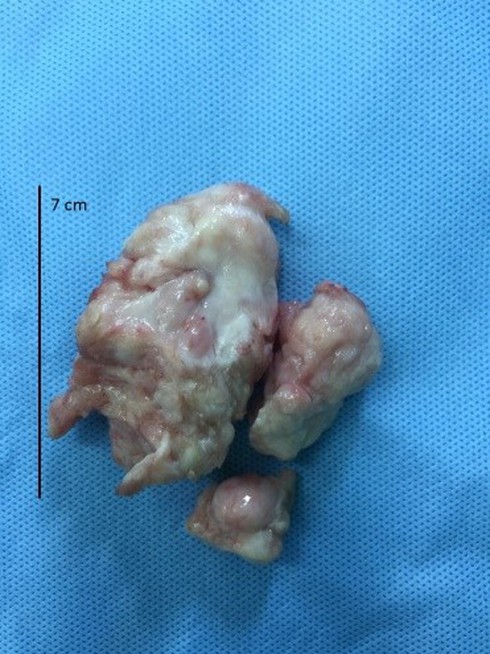

Khối u trong tim của bé sau khi được lấy ra |

Sau hơn 4 giờ phẫu thuật cho bé, toàn bộ khối u đã được lấy ra khỏi tim. Phần buồng tim còn lại đã được sửa chữa để đảm bảo chức năng tim được bình thường. Các bác sĩ rất bất ngờ vì bé có thể sống được với khối u lớn như vậy và cũng may mắn là kết quả xét nghiệm mô học cho thấy đây là u sợi lành tính.